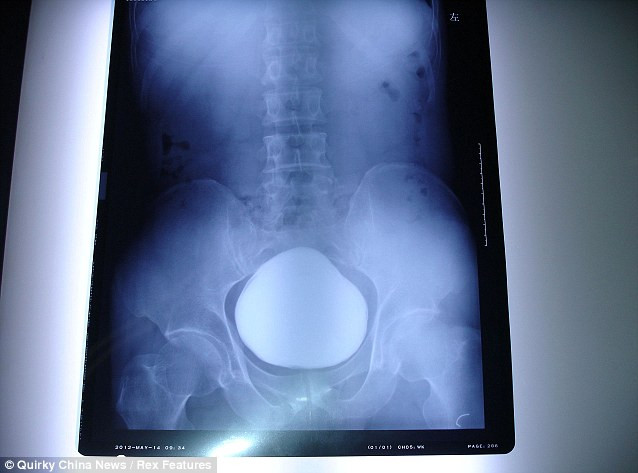

| Phim X-quang cho thấy viên sỏi bàng quang trong người bệnh nhân 43 tuổi ở Vũ Hán. |

Các bác sĩ thừa nhận rằng họ đã vô cùng sửng sốt khi lấy viên sỏi bàng quang kỷ lục trên ra khỏi cơ thể của người đàn ông 43 tuổi họ Zhang tại Vũ Hán, tỉnh Hồ Bắc, Trung Quốc.

Người đứng đầu nhóm phẫu thuật, bác sĩ Wu Tianpeng cho biết, đây là viên sỏi bàng quang lớn nhất ông từng nhìn thấy và là viên sỏi bàng quang nặng thứ 2 được phát hiện tại Trung Quốc. Nó có đường kính lên tới 11 cm.

Theo tiến sĩ Wu, bàng quang người thông thường chỉ có thể chứa 300-500 ml nước tiểu và tối đa là 1.000 ml. Tuy nhiên, viên sỏi nặng 1,025 kg của ông Zhang đã chiếm phần không gian tương đương với 700 ml nước trong bàng quang và khiến ông thường xuyên thấy đau buốt.